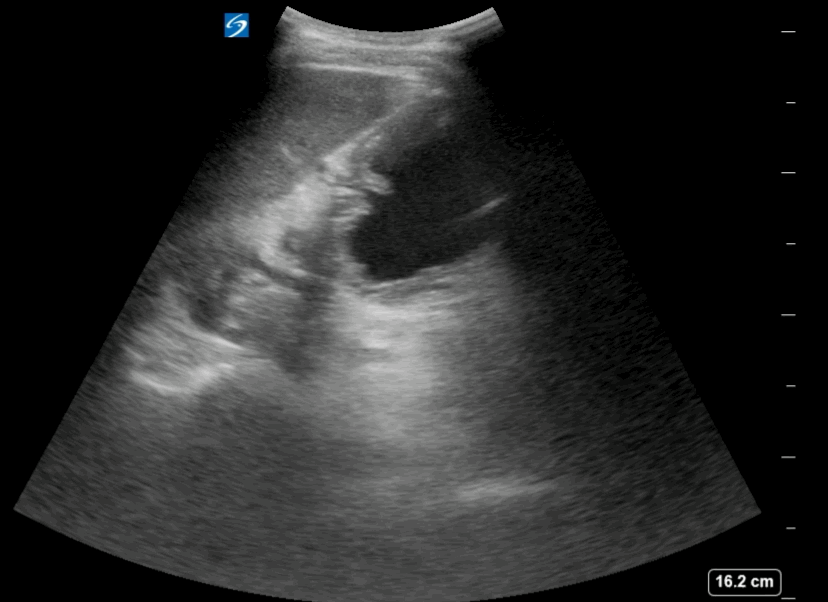

- Is the stomach empty or full ?

- If clear fluid is present in the stomach – calculating the volumen in the stomach

- Does the content in the stomach represent a risk for the patient ?